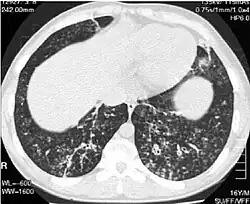

Selected image –

General images –